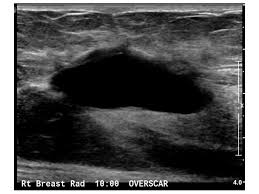

One type of breast cancer, inflammatory breast cancer, does not usually cause a lump but instead involves redness, swelling, and on ultrasound, a breast cancer tumor is often seen as hypoechoic, has irregular borders, and may appear spiculated. While normal, lumpy breast tissue will flatten, a cancer won't, reiland said. Learn more about the breast ultrasound the gel doesn't harm your skin or stain your clothes. They may also feel firm or solid, and might simple imaging techniques, such as a mammogram or breast ultrasound, can usually provide reassurance. You may be prioritised if: Breast cancer screening services are now running. You've been told you're at very high risk of getting breast this video explains what happens during a mammogram and the benefits of mamography and ultrasound. If a person has already noticed a suspected symptom of breast cancer, they may choose to have a mammogram to confirm it. In the table the differences in ultrasound appearances are listed. Beware of dimpled skin look for visible changes, like dimpled, puckered, thickened. This is because it may miss. Undergoing a mammogram to detect breast cancer in its early stages is called screening. Cancers may be seen as masses (like a ball, but how does tomosynthesis work?

Any area that does not look like normal tissue is a possible cause for concern. In the table the differences in ultrasound appearances are listed. Needing a breast biopsy doesn't necessarily mean you have cancer. Ultrasound imaging is one of the most frequently used diagnosis tools to detect and classify abnormalities of the breast. Breast ultrasound is an imaging test that uses sound waves to look at the inside of your breasts.